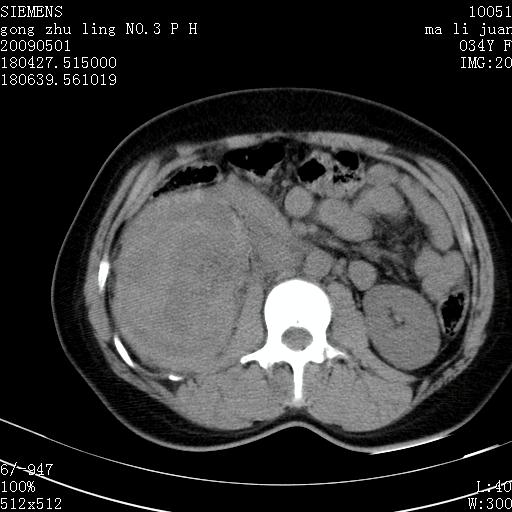

标题: CT19733:右肾碎裂

青年女性,骑摩托车摔伤。

右肾碎裂伤,包膜下血肿。

术中仅见右肾碎裂,肾蒂血管未见断裂。